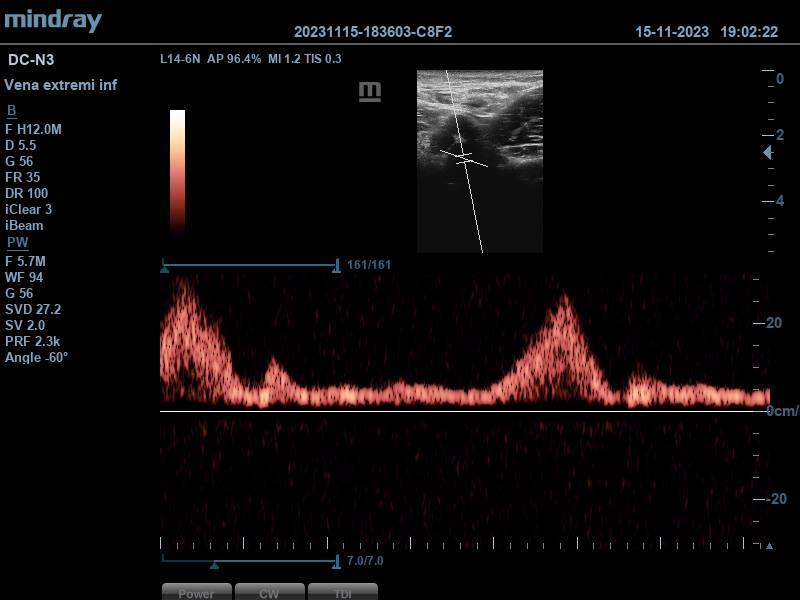

Se aplica Doppler pulsado, obteniéndose dos espectros compatibles con vasos arteriales (correspondientes a la arteria femoral superficial y femoral profunda), y otros dos espectros con patrón sugestivo de flujo venoso, que aumenta con la compresión del gemelo, generando picos de flujo. Todo ello, hace pensar en que estamos ante una duplicidad femoral.